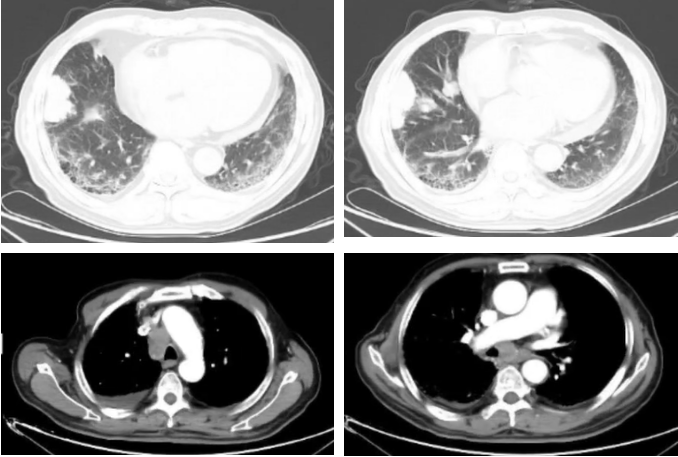

2023-02-28胸部+上下腹增强CT:恶性肿瘤维持性化学治疗后,较2022-11-15日胸部CT,右肺中叶斑片影范围增大;右肺门淋巴结增大;右侧胸腔积液增多:心包积液减少;双肺间质性改变同前,余较前变化不大。胰尾旁多发结节,考虑MT可能。肝门区及腹膜后淋巴结稍大。左侧肾上腺结节样增厚,双侧部分肋骨、右侧髂骨高密度影,建议定期复查。肝S7段脂肪瘤。

图4

2023-02-24颅脑增强MR:较2022-3-30日MR旧片,新增左侧侧脑室旁异常信号影,考虑腔隙性梗塞灶;余未见明显变化。